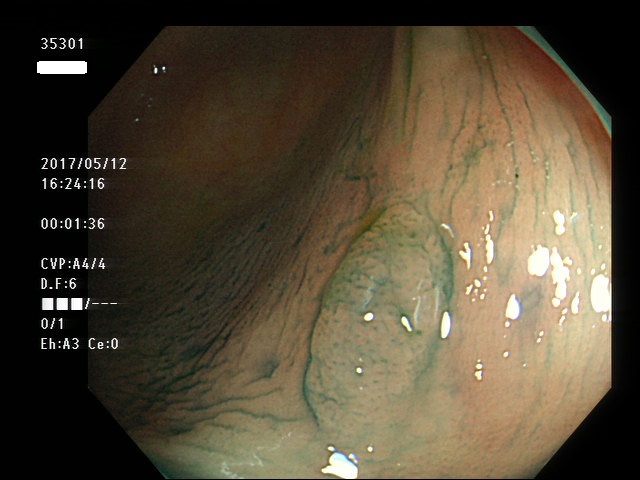

左側に小型の過形成が数十、多発する。個々の過形成が直接、癌化するリスクは低いが、腸全体が腫瘍が出来易い体質であることが多く、腺腫および腺腫由来の癌が出来易い。また遺伝的にDNA修復機能の低下が見つかることもある(文献